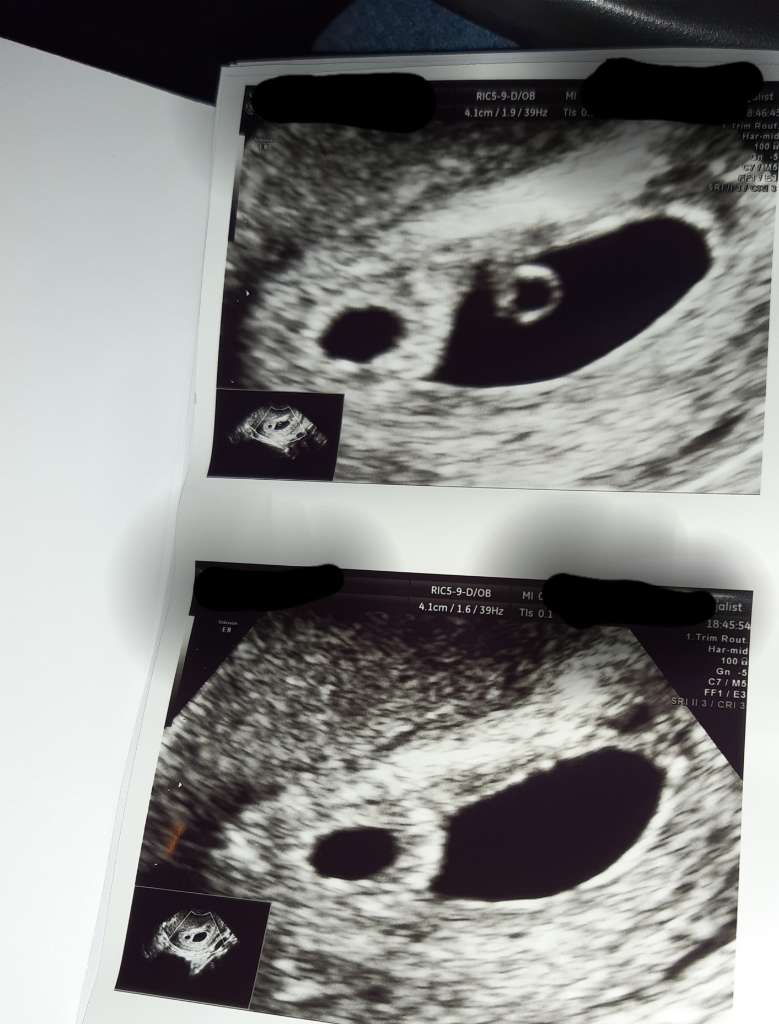

Test powtórzony pół godziny temu, no raczej poprzedni nie był wadliwy... Jeszcze jeden zostawiłam na jutro rano, choć raczej na pewno będzie też będzie pozytywny.

Zobacz załącznik 1453900